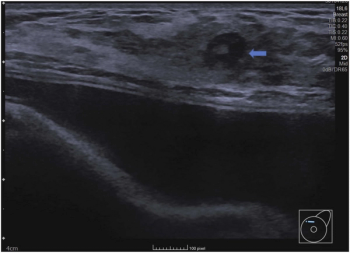

Emerging research suggests that stand-alone artificial intelligence (AI) assessment of breast ultrasound exams could eliminate over 45 percent of unnecessary follow-up exams.